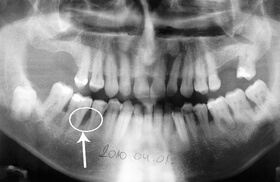

Féléves kontroll felvétel a regeneratív műtét után. A csontkráter kitelődött csonttal, azaz a defektus meggyógyult